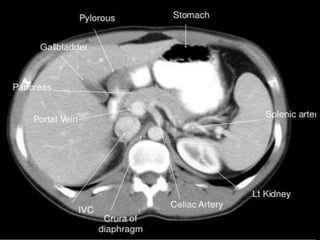

CT cross sectional anatomy.

MRI anatomy images of the abdomen.

CT – computedtomography. •Cross-sectional modality with capabilities for multiplanar reconstruction and dynamic imaging to assess vascularity •Tube rotates around the body and a circle of stationary detectors detects the penetrating x-rays forming an image.

MRI anatomy imagesof the abdomen.